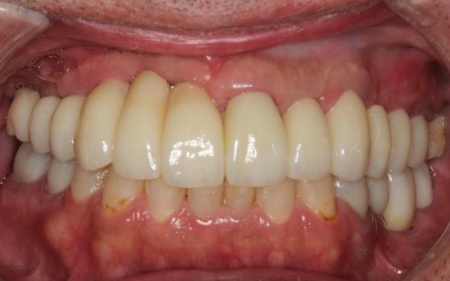

50代男性 バランスが崩れた噛み合わせをインプラント治療と被せ物治療で改善した症例

- 骨再生

- 詰め物・被せもの

- セラミック・ジルコニア

- インプラント

- サイナスリフト

- ダイレクトボンディング

- 治療期間の目安 3年

- 治療回数の目安 約45〜50回

-

治療費総額の目安

約4,479,545円

【内訳】

サイナスリフト、骨移植、インプラント6本、他院インプラント人工歯作り替え、ジルコニアクラウン(インプラント人工歯6本、被せ物3本)、ダイレクトボンディング

治療のリスク

・外科手術のため、術後に痛みや腫れ、違和感を伴います ・メンテナンスを怠ったり、喫煙したりすると、お口の中に大きな悪影響を及ぼし、インプラント周囲炎等にかかる可能性があります ・糖尿病、肝硬変、心臓病などの持病をお持ちの場合、インプラント治療ができない可能性があります ・高血圧、貧血・不整脈な...

by.鈴木歯科医院